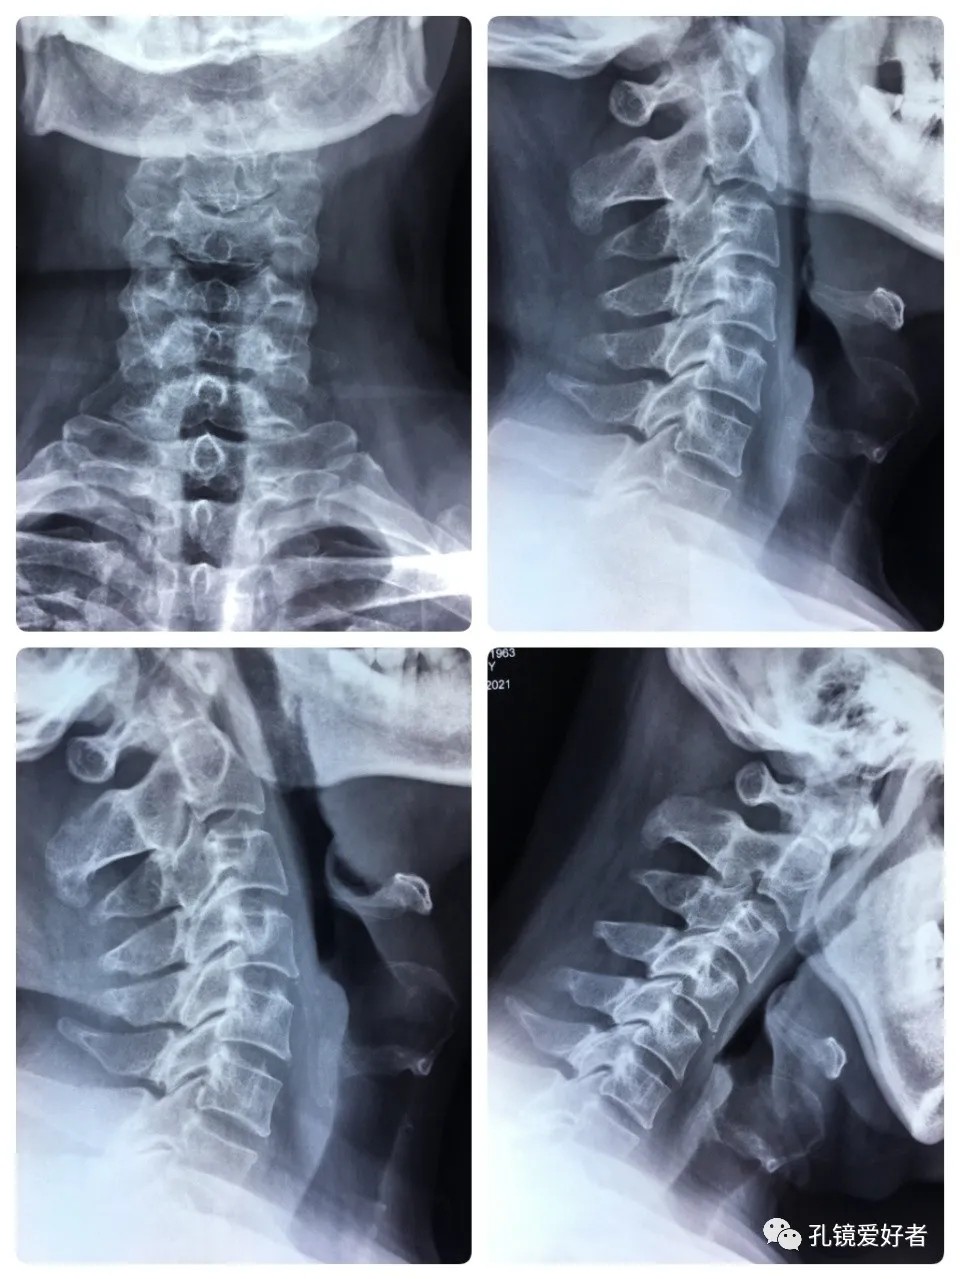

The patient's preoperative imaging data

The PA and lateral and flexion-extension position of cervical spine

CT imaging mainly focused on a plain scan of the cervical spine, and there is no scan on the intervertebral space.